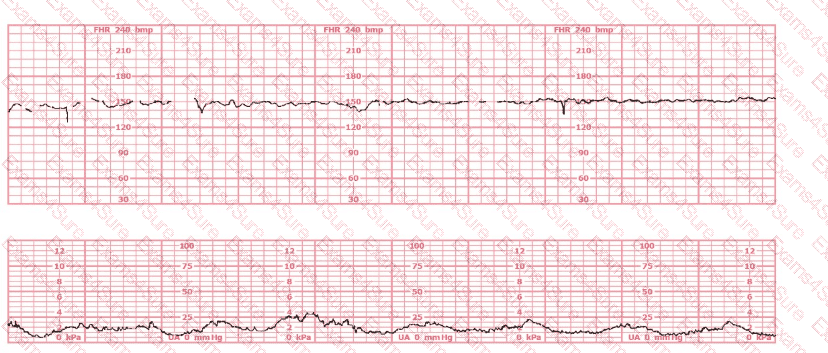

This tracing has lasted for 20 minutes in a woman who is 6 cm dilated. The most appropriate intervention is: